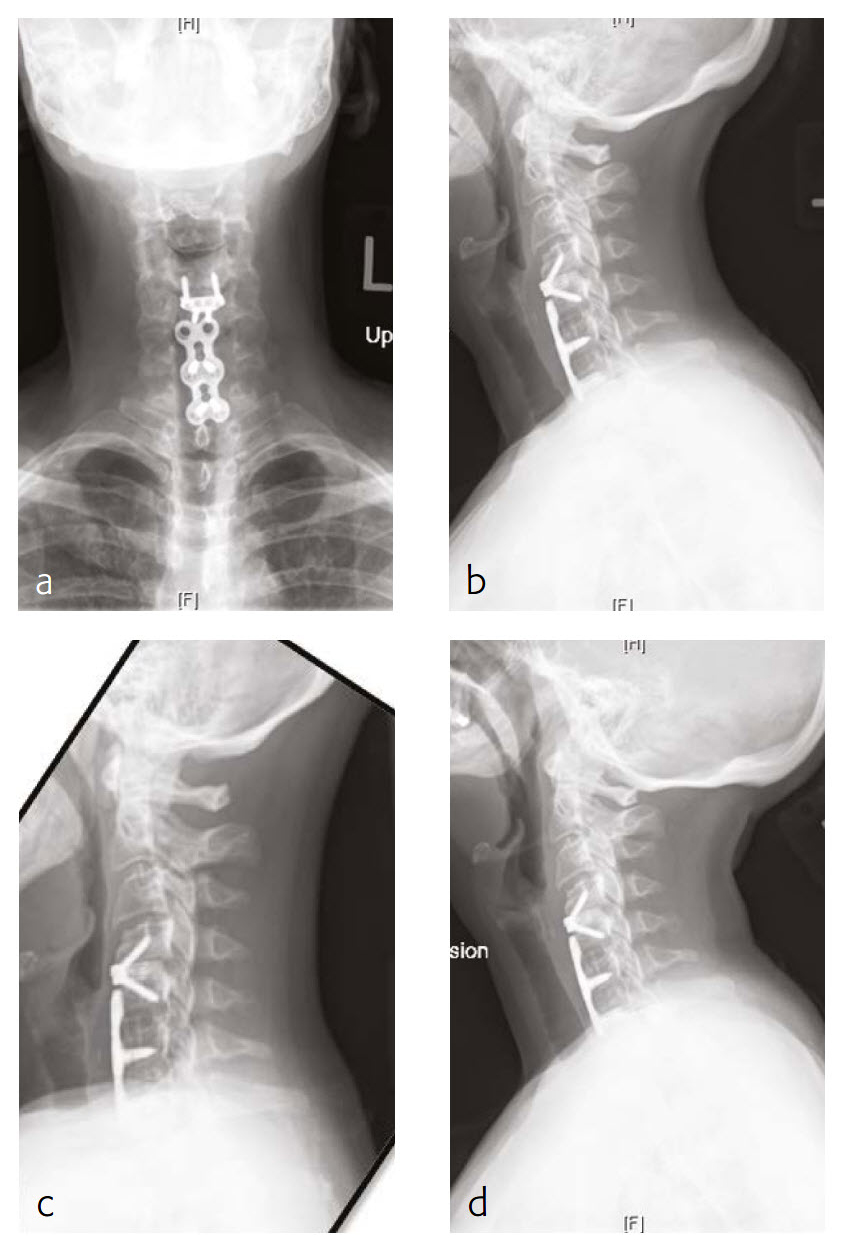

Case 1: Progressive shoulder and arm weakness with neck pain

A 56-year-old man, partly left-hand dominant partly right-hand dominant depending on the activity, presented with progressive left shoulder and arm weakness with pain radiating from his neck down to his left shoulder and an EMG documenting a left C5 radiculopathy (Fig 1).

The patient claimed a normal state of health until 5 weeks previous. This then began to backtrack to the neck and to develop weakness in his left arm to the biceps and deltoid. On examination, the patient had 4/5 deltoid and biceps strength on the left and decreased sensation along his lateral shoulder.

The patient showed normal lordosis in his extension x-rays. He has approximately 2 mm of anterolisthesis of C4 on C5 in his extension on his flexion x-ray. This increases to approximately 56 mm and persists in his normal upright film with again some component of spondylolisthesis at that level.

The patient's earlier MRI shows severe left-sided C4-C5 foraminal stenosis and multilevel disc degeneration with very mild central narrowing at C3-C4, C6- C7, and C7-T1. He also has a small right paracentral disc herniation at C6-C7.

The new MRI of the C4-C5 showed mild uncovering of the disc posteriorly due to grade 1 anterolisthesis. There is also mild left facet arthropathy with left uncovertebral joint osteophytes resulting in moderate left neural foraminal narrowing. The right neural foramen is adequately patent.

Follow-up (4 months)

At the patient follow-up at 4 months postoperative, he described complete resolution of left upper extremity pain (Fig 2). He was also happy with his left upper extremity strength and was extremely pleased with his progress. He continued to have no left upper extremity pain. He also believed that he had made significant progress in terms of his left upper extremity range-of-motion and strength.